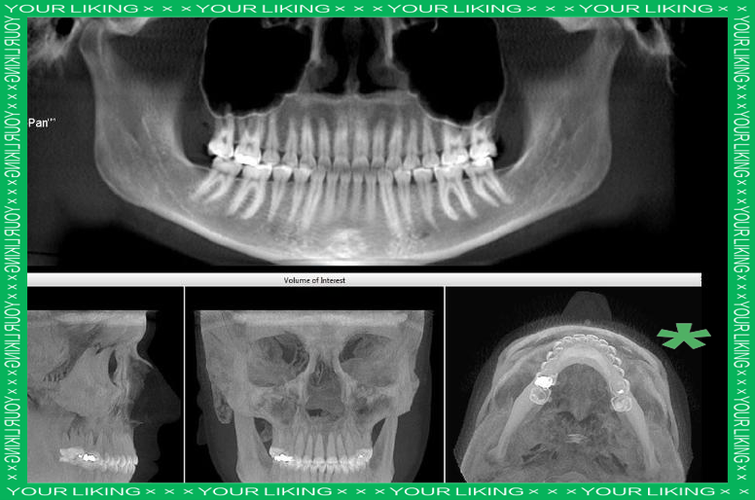

- 权衡利弊:牙医开具全景片检查,是为了获得诊断疾病和制定治疗计划所必需的全面信息,其带来的诊断价值远远大于其微乎其微的辐射风险,没有这些影像,可能会漏掉重要的疾病(如埋伏牙、囊肿、肿瘤、严重的牙槽骨吸收等),导致更严重的后果。

- 儿童:儿童对辐射比成人更敏感,但儿童在正畸、拔除多生牙等治疗中,全景片又是必不可少的,牙科医生会遵循“ALARA”(As Low As Reasonably Achievable,合理可行尽量低)原则,使用儿童专属的更低剂量参数,并严格遮盖甲状腺等敏感部位。